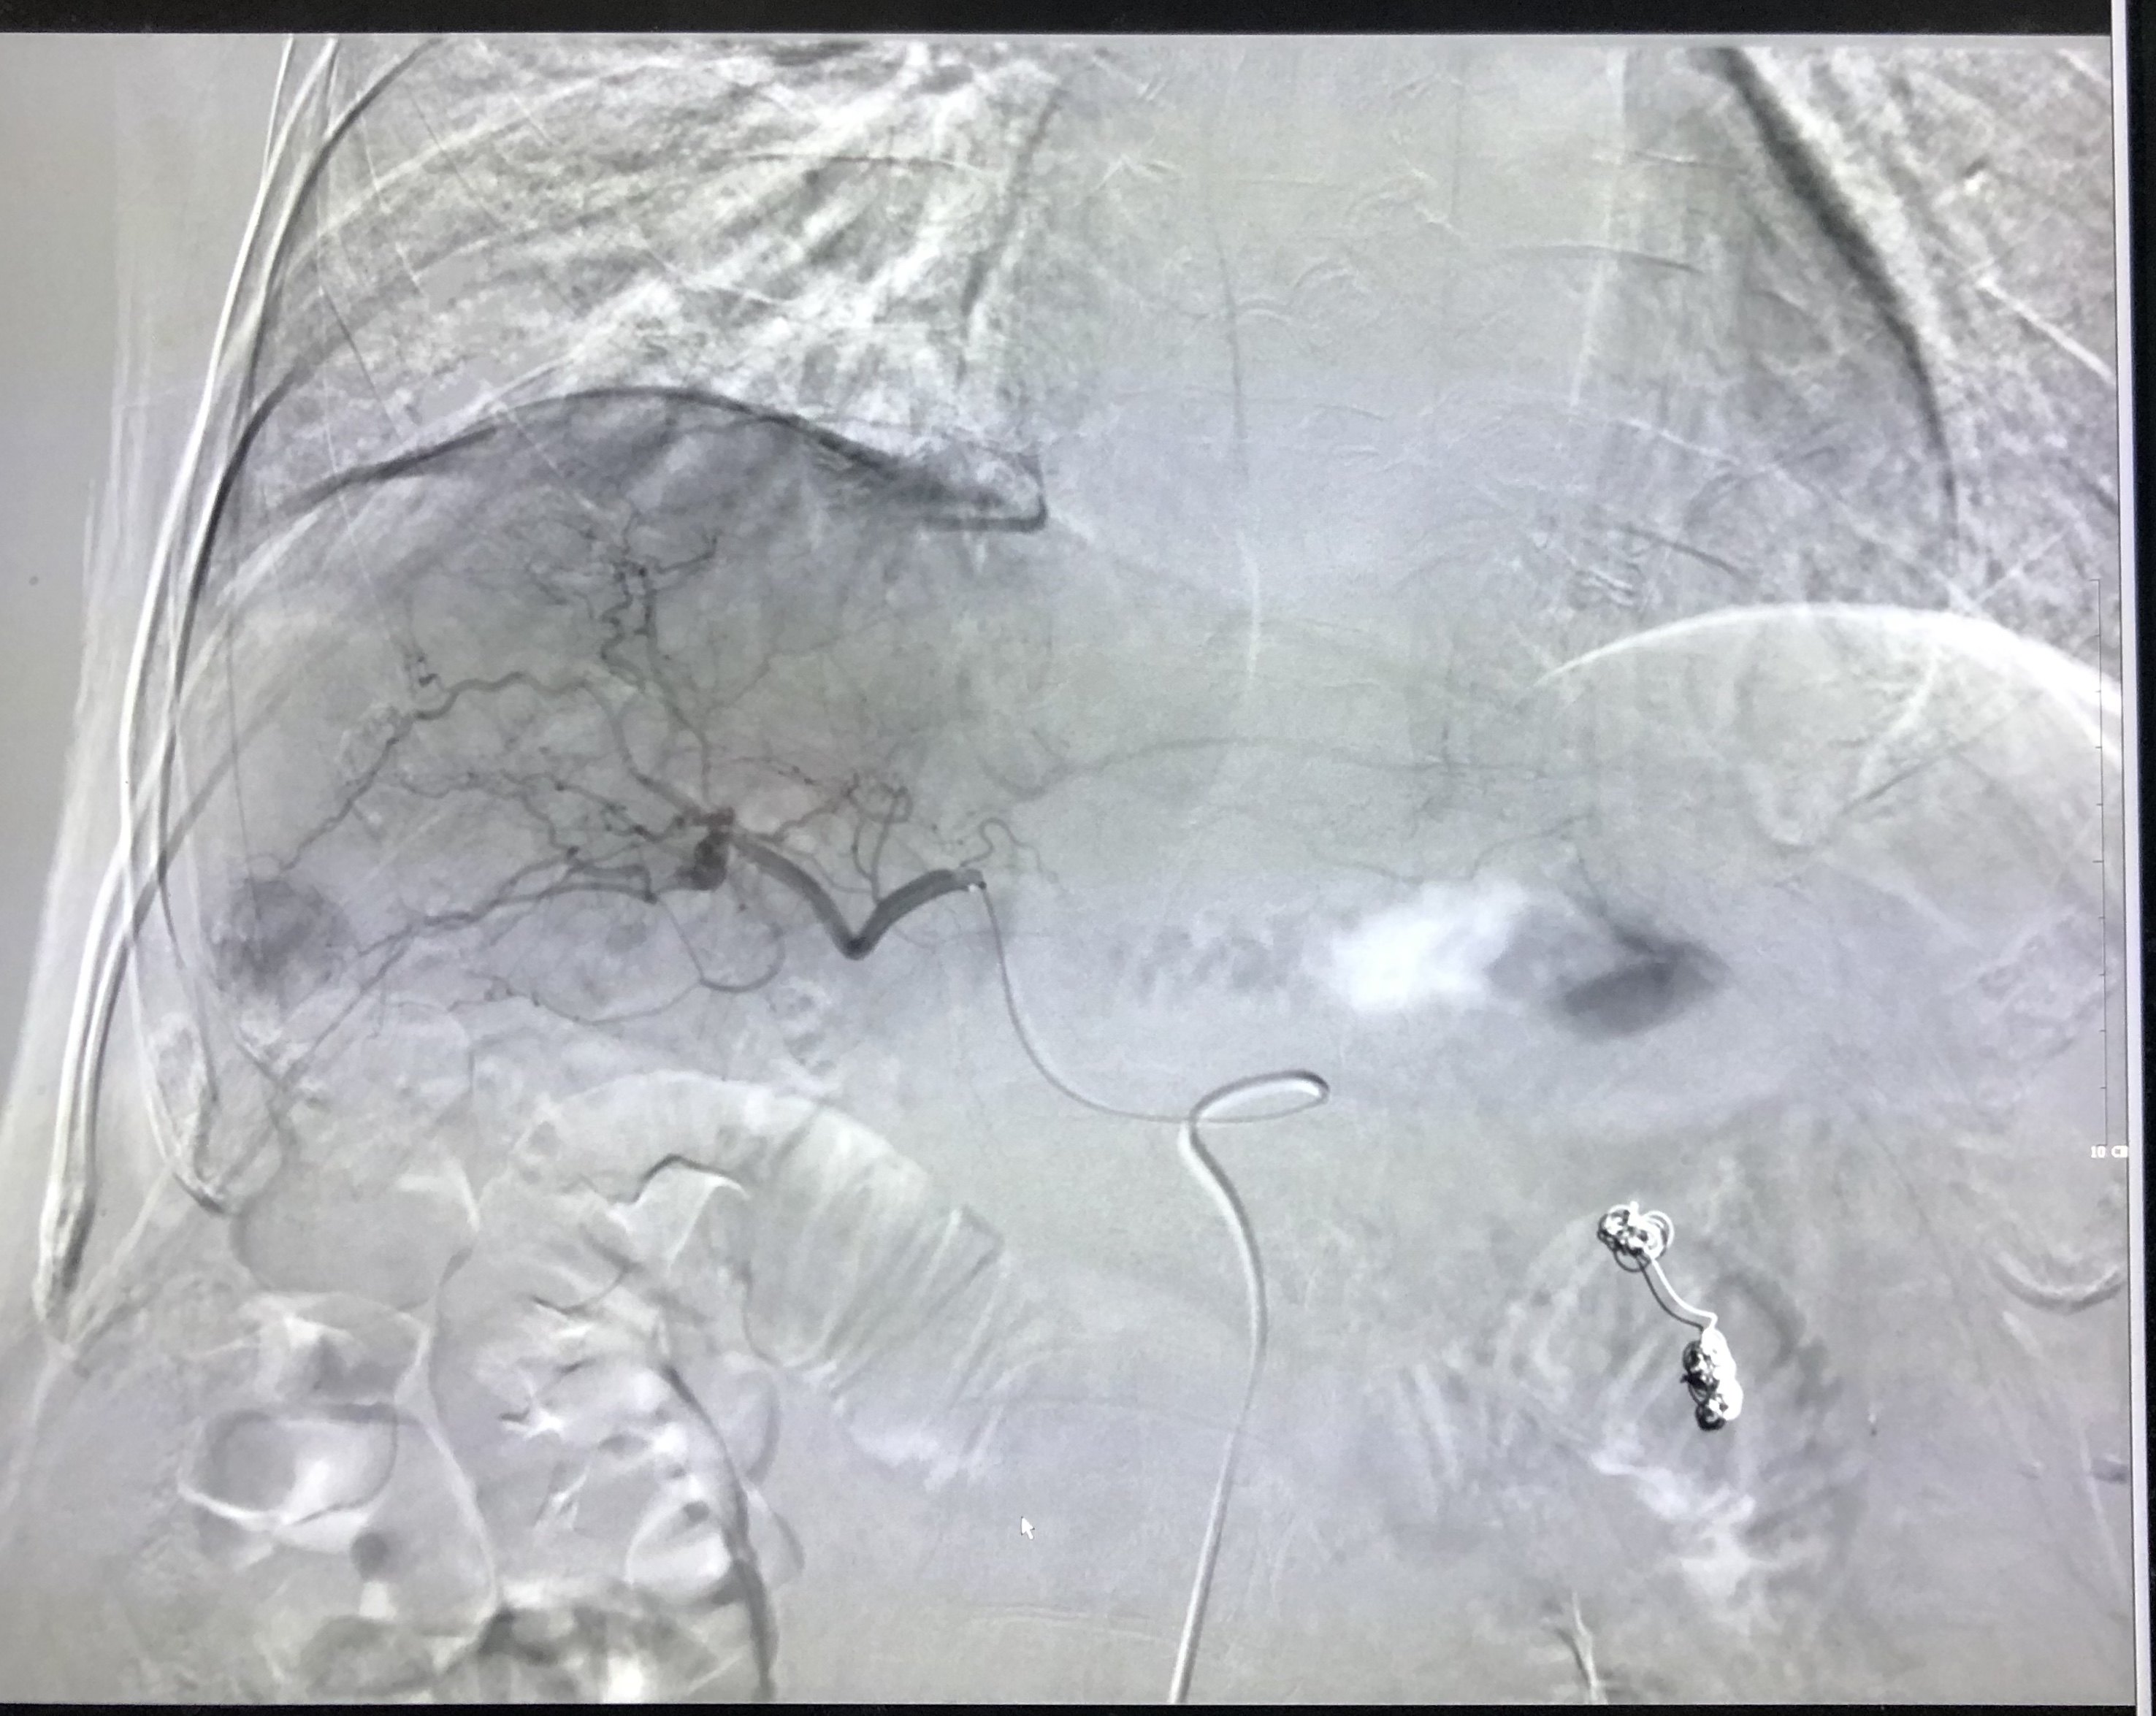

腹腔动脉造影见脾动脉粗大,肝动脉细小,提示脾动脉盗血综合症。

行脾动脉主干栓塞部分阻断脾动脉血流。